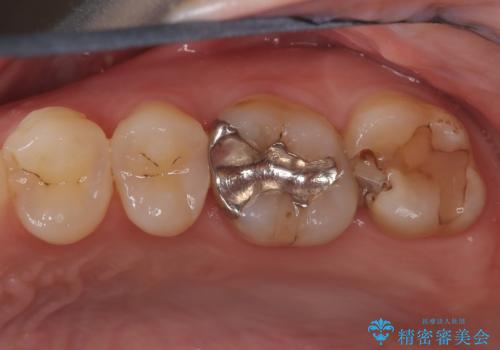

奥歯の銀歯を美しく一新!歯の破折を防ぐセラミッククラウン

担当医 河口智英